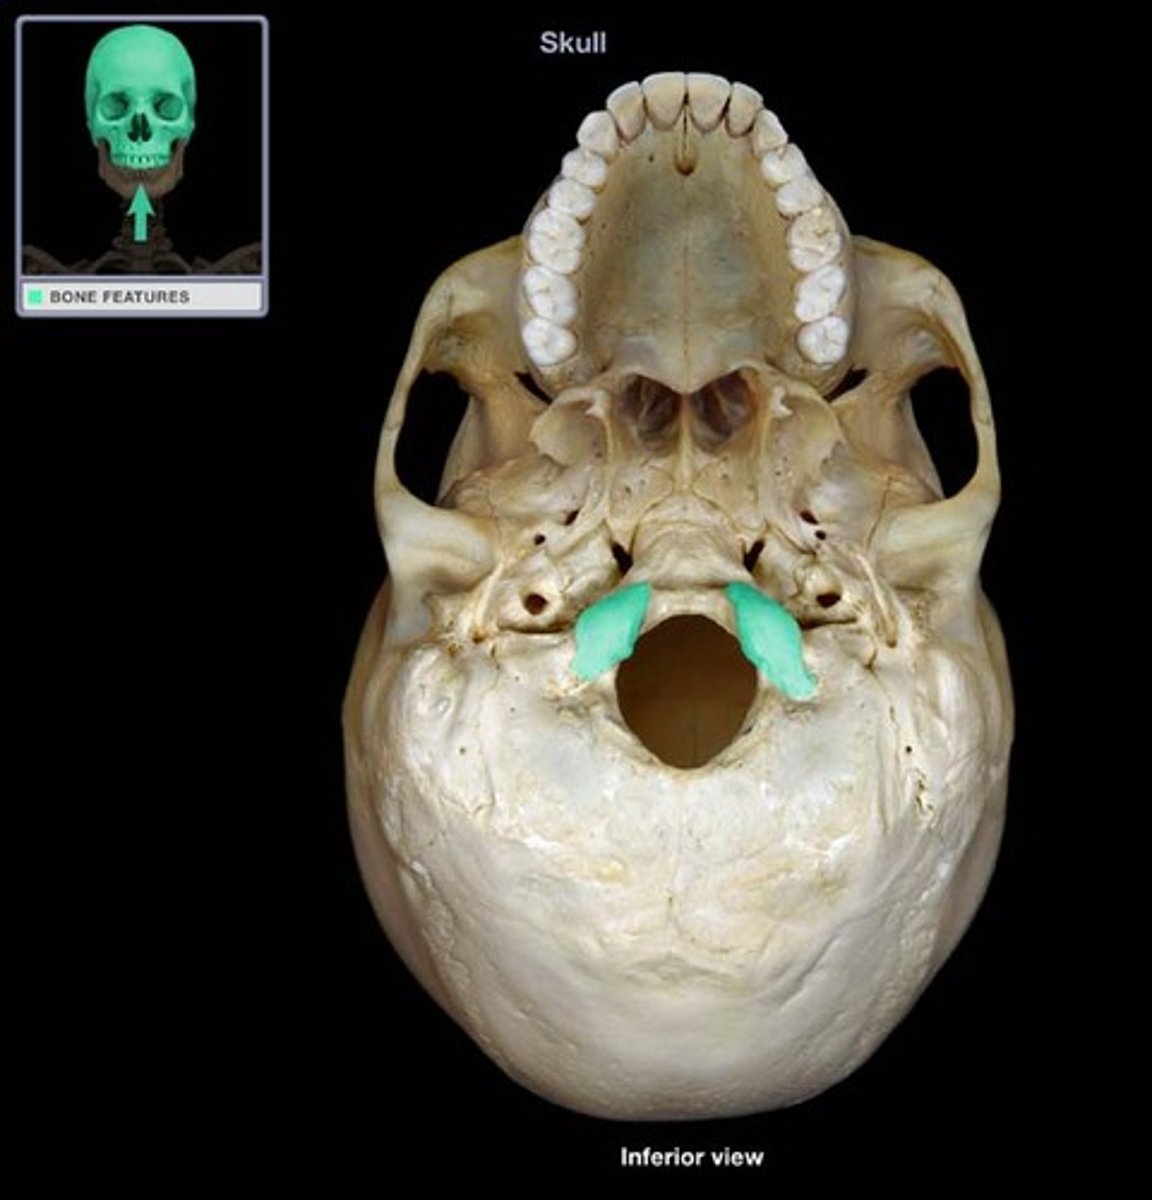

os sphenoidale

pleištakaulis

Foramen magnum

Didžioji anga

Condylus occipitalis

pakauškaulio krumpliai